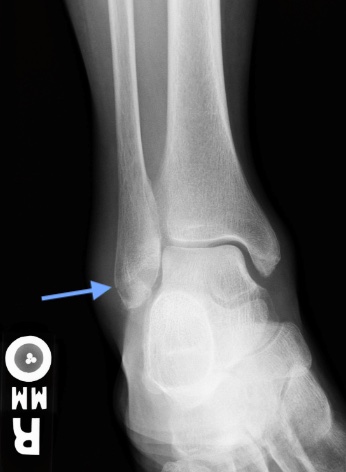

Answer: Weber A (Lateral Malleolus/Distal Fibula) Fracture